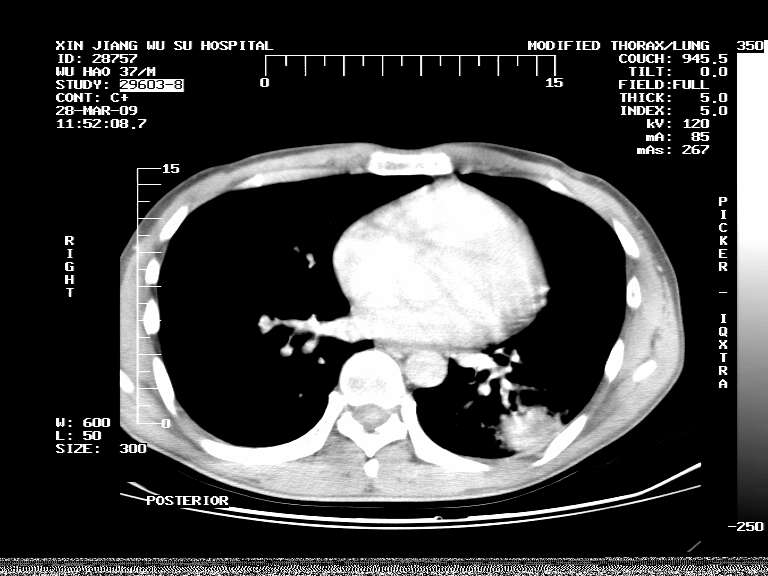

男,37岁,体检胸透发现阴影。

患者体检发现 无症状 左肺下叶占位,边缘模糊,可见血管聚束、分叶、胸膜牵拉,增强呈不均匀性强化。 首先考虑左肺下叶周围型肺癌,建议穿刺活检。

考虑左肺下叶感染性病变伴局部胸膜反应;建议抗炎治疗后复查,排除周围型肺癌。

左肺下叶见一结节病变,边缘欠清不光滑,与胸膜粘连且胸膜局限性增厚,注药后呈环形强化,动脉期壁呈明显点环状强化,静脉期壁强化减低,中心密度低无强化,灶周无明显的卫星灶和水肿区(晕征)---考虑周围性肺癌,不除外感染性病变,建议穿刺活检。

左肺下叶结节影.密度不均,边缘不规则.周围少许渗出.考虑感染性病变.结核?肿瘤待排.